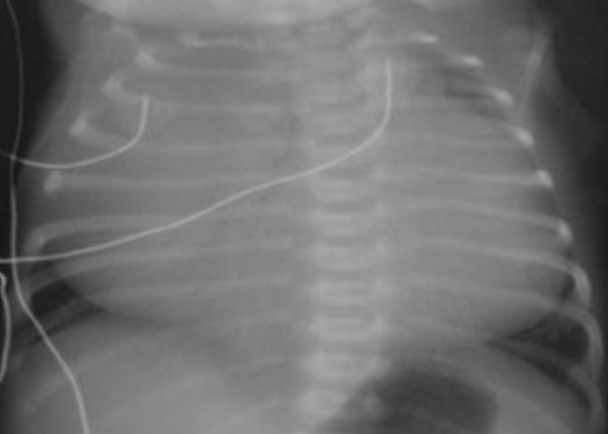

- AP chest film showing that the naso-gastric tube (NGT) is inside the left - (1 hemi-thorax. There is an ill-defined line separating the upper and middle .zones of left lung

- The diagnosis was ruptured left hemi-diaphragm possibly secondary to - (2 .the trauma to the abdomen

- During surgery, there was a ruptured diaphragm and intestines, spleen - (3 and stomach were found in the left chest. There was evidence of left sided .CDH which facilitated the rupture